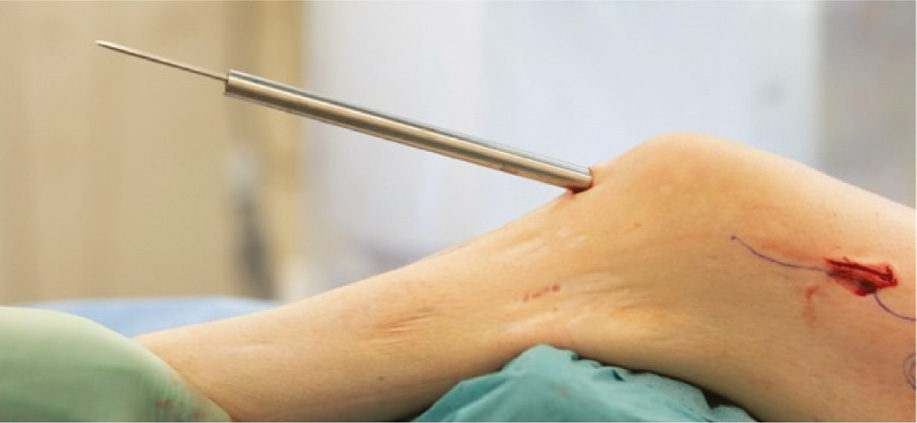

Figure 23. Once one of the distal screws/pegs is removed, the nail insertion incision is re-opened and a 3.2 mm K-wire is placed through the patella tendon.

jposna20220031_fig23.jpg